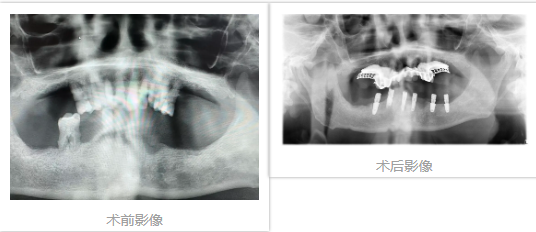

案例二

患者,李女士,66岁,下牙列缺失,先后两次做活动牙,因无法适应而选择种植。